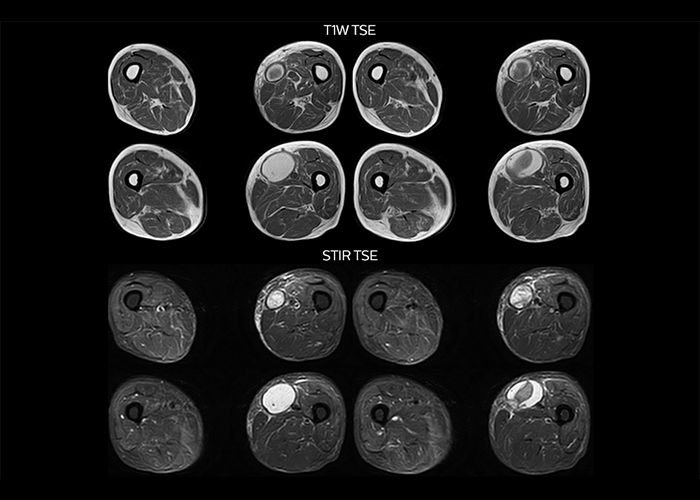

“On average, we scan about 80 patients per day, but on some days we scan well over 100 patients. The scanner is in use 7 days per week, operated 20 hours per day on week days and 8 hours per day in the weekend,” Mr. Tuna says. “To avoid coil changes we plan examinations of similar anatomies back to back, such as head and spine. Multiva helps us here a lot because coils don’t need to be changed frequently. Moreover, thanks to parallel imaging technology and 16-channel HeadSpineTorso and 8-channel MSK coils we are able to achieve excellent image quality. In this way Multiva helped us to increase both image quality and productivity.” “Neurological cases, such as brain and spine imaging, represent the largest share in our MR scanning, followed by musculoskeletal cases. In general, we use simple and basic imaging protocols. But occasionally, we use advanced techniques for problematic cases if necessary.

“Since we have Multiva, we have improved our workflow, because it has been so easy for our operators to learn and use Multiva. Our operators notice that the coils are lightweight and coils don’t need to be changed frequently. The user interface is easy to use. Features like this help us to scan a high number of patients. For instance, the musculoskeletal coils can be used interchangeably, and due to the user-friendly interface, the number of mistakes such as, for example, correct coil element selection has decreased significantly, because the system does it automatically by itself.” “Most important, Multiva satisfies our clinical imaging needs very well,” says Mr. Tuna. “Many features of Multiva have become similar to the Ingenia system. Even in more complex imaging such as abdominal and cardiac, the image quality and performance of Multiva is better than we expected. General surgeons and physicians from our hospital’s internal medicine department prefer to refer to us because of this.”